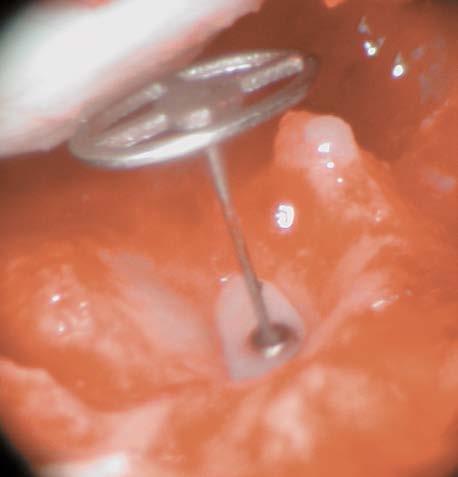

SIZER OMEGA CONNECTOR

SECURE CONNECTION WITH THE STAPES FOOTPLATE

The OMEGA CONNECTOR (see page 18-19) creates an optimized connection with the stapes footplate for KURZ Total Prostheses (with the exception of the Regensburg Total). To obtain a secure fit on the stapes footplate appropriate spatial conditions must be considered.

PRECISION REFERENCE MEASUREMENT

The Sizer OMEGA CONNECTOR was developed for managing the spatial limitations. Length and width of its measuring tip are equivalent to the dimensions of the OMEGA CONNECTOR.

EASY TO USE

The instrument is placed onto the footplate to determine ample footplate space for the OMEGA CONNECTOR. It is made of stainless instrument steel and can be resterilized.